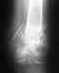

Гонартроз в начальной стадии, отек подколенной ямки и, как следствие, нарушение венозного оттока, увеличение голени в объеме

После существенных нагрузок на ноги внезапно возникла боль в области свода стопы, после чего появился отек под коленом спереди и в области подколенной ямки. Терапевт отправила к хирургу, хирург отправил к сосудистому хирургу, который визуально поставил диагноз варикоз, выписал детралекс и компрессионные колготки и отправил лечиться. По истечении 2 месяцев ситуация не улучшилась, отправилась к другому врачу, который сообщил, что у меня лимфостаз, посоветовал антистакс и лечение аппаратной компрессией. Данное лечение ухудшило ситуацию, боли стали постоянными, отеки на ноге не исчезли. После чего были консультации с другими врачами, эндокринологом, нефрологом ( который выявил нарушение уродинамики правой почки - почка оперированная и хронический пиелонефрит), ревматологом (который выписал терафлекс, аркоксию и компрессы с димексидом). Все выше перечисленные мероприятия ситуацию не улучшили, было проведено МРТ ( процедура, которая и выявила, собственно гонартроз) и КТ с контрастированием, которая никаких нарушений, кроме начальной стадии остеоартроза коленного сустава, не выявила). Температура ежедневно вечером 37,2-37,4, давление утром 130/100, вечером 140-150/100-110. Два дня назад начала вздуваться вена на стопе. подколенной ямки и коленного сустава). Сегодня сделали инъекцию в область подколенной ямки и в сустав. Обращаюсь к врачам, встречавшимся ранее с такой проблемой, как у меня, к опытным врачам. В чем может быть вероятная причина моего недуга? Как справиться с данным заболеванием? Адекватно ли, по Вашему мнению, такое лечение? Состояние ноги не улучшается в течение 7 месяцев.